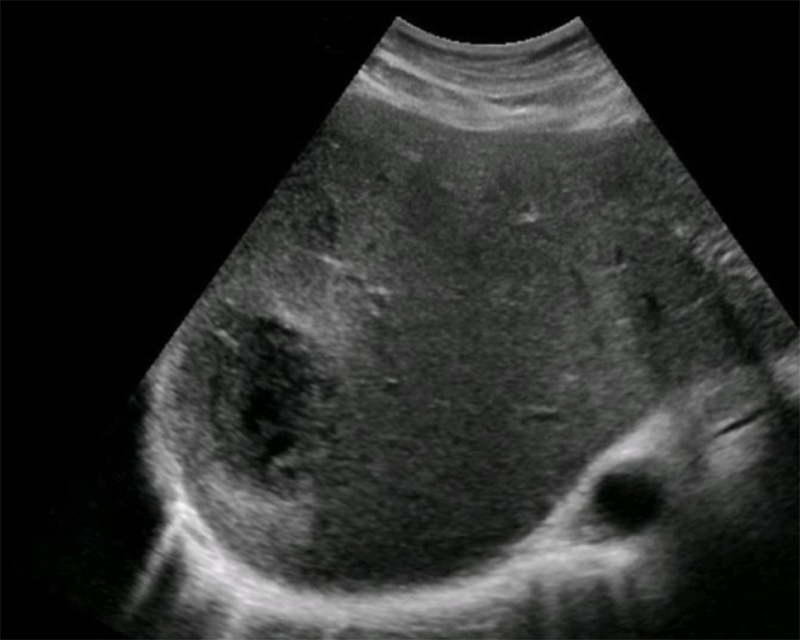

- Amoebic abscess4

- Prevalent in sub-Saharan Africa, Indonesia, Indian subcontinent, Mexico, and parts of Central and South America.18

- Often presents 2-3 weeks after intestinal amoebic infection with fever, RUQ pain, and jaundice.

- Most often single, usually in the posterior right lobe.

- Thin or invisible wall, hypoechoic, more uniform texture.

- More common than pyogenic abscesses in the tropics.

Figure 28. Well-defined hypoechoic fluid collection in the right liver lobe, with central fluid, complex periphery, and a thin wall representing an amoebic abscess. (Liver Imaging Atlas, www.liveratlas.org. Copyright 2010. Image used with permission from University of Washington. Accessed 4/14/21)

- Hydatid cyst (see section below)